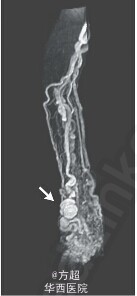

近日NEJM报道1例罕见病例,同大家分享一下:老年女性,因指尖溃疡就诊,患者自诉左臂自幼年起即出现动静脉畸形。查体可见肥大病变,累及手指、前臂、肘部,同时上臂巨大动静脉畸形(搏动性,伴明显的静脉、动脉扩张,血管震颤)。磁共振血管成像可见肘部、前臂、手扩张、扭曲的动脉和静脉,并出现多处动脉瘤性扩张及高流动量的动静脉短路;考虑为帕-韦二氏综合征,即血管-骨肥大综合征。该患者拒绝接受手术治疗,仅要求对指尖溃疡包扎后离院。 帕-韦二氏综合征的病变包括静脉和毛细血管畸形,伴高流量动静脉短路,以及相关肢体可能出现的过度增生,多数为散发病例,常累及下肢,可能与遗传因素相关,但该病累及手臂情况较为少见,该病例如此血管扩张畸形较为罕见,可能与病情较长相关。Stefan Stefanov-Kiuri, M.D., and Alvaro Fernandez-Heredero, M.D.N Engl J Med 2014; 371:2114。